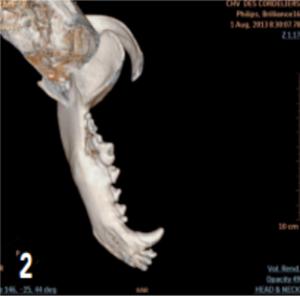

Le scanner a révélé la présence d’une lyse osseuse de l’os alvéolaire mandibulaire s’étendant de la racine dorsale de la carnassière jusqu’à la racine caudale de la deuxième prémolaire (photos 2 à 6).

Photo 2 : Reconstruction en 3D montrant la lyse osseuse de la mandibule s’étendant de la carnassière à la deuxième molaire.